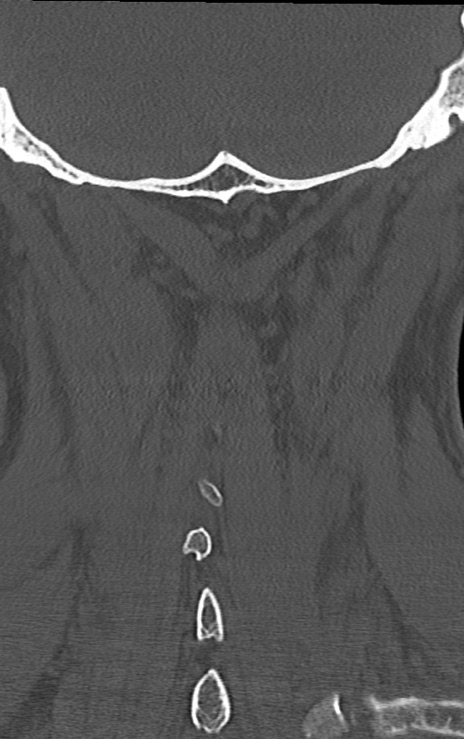

【整形】TIPS症例7 頚椎CT(冠状断像)

【症例】60歳代男性

【主訴】両手のしびれ

【現病歴】15年前より右手のしびれあり。4ヶ月前から左手のしびれあり。最近、症状増悪あり。

【身体所見】BTR+/+、BRR+/+、TTR+/+、PTR ++/++、ATR ++/++、Babinski-/

頚椎CT